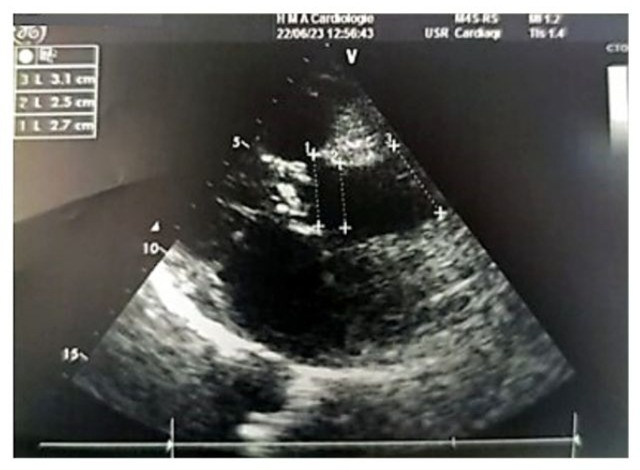

Left ventricular filling pressures were normal, and the inferior vena cava was dilated to 16 mm and slightly compliant. (Figure 3,4) The left atrium was dilated, with a surface area of 21.5 cm² and a volume of 44 ml/m². (Figure 5) The right ventricle had preserved systolic function with a TAPSE (Tricuspid Annular Plane Systolic Excursion) of 22 mm and a tissue Doppler S’ velocity of 12 cm/s. The right atrium was dilated at 19.7 cm², free of echoes. Assessment of the valvular apparatus showed a tricuspid aortic valve with degenerative changes, including calcified masses between the right and left cusps, limiting valve opening. Severe stenosis was noted, with a valvular area of 0.8 cm² (indexed area of 0.58 cm²), a Vmax of 3.93 m/s, and a mean gradient of 35 mmHg. The aortic annulus measured 19 mm, and minimal regurgitation was observed. (Figure 6-9)

Figure 8: 2D echocardiographic image in the parasternal long-axis view showing a non-dilated proximal aorta. The aortic annulus measures 2.7 cm, the sinus of Valsalva 2.5 cm, and the tubular segment 3.1 cm.